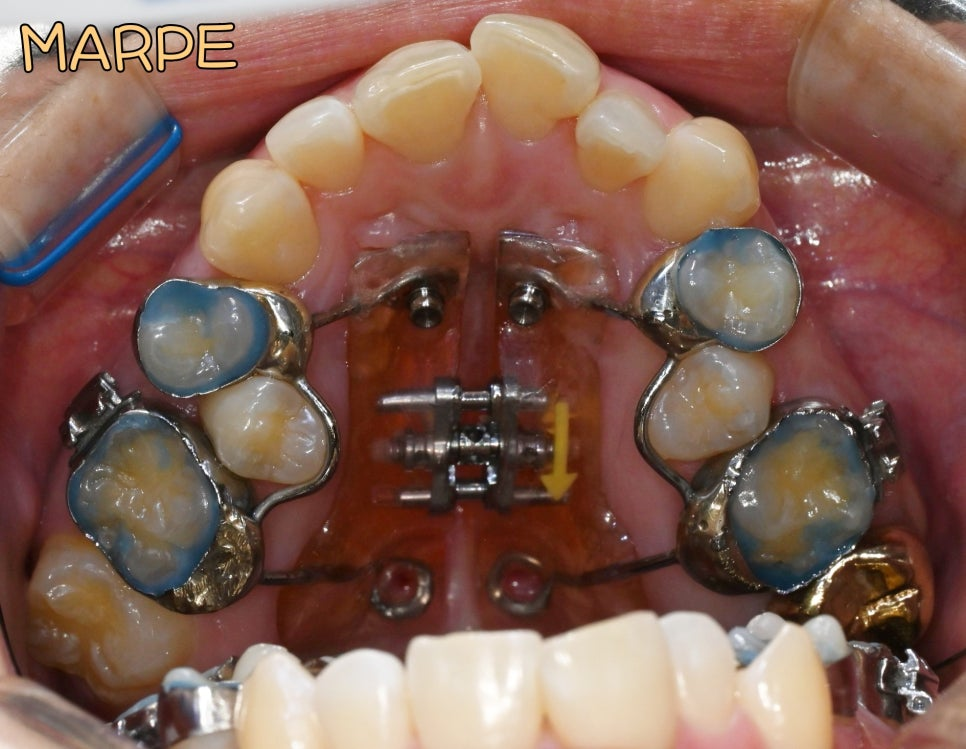

치료는 계획대로

MARPE 장치를 이용한

상악골 확장부터 시작되었습니다.

위턱에 4개의 미니스크류를 식립하고

확장장치를 장착한 후

단계적으로 확장을 진행했습니다.

초기에는 확장장치가 정상적으로 작동하며

어느 정도의 확장이 이루어지는 것처럼 보였습니다.

그러나 확장 과정에서 예상보다

저항이 크게 나타났으며,

충분한 골격적 확장에 도달하기

어려운 상황이 되었습니다.

성인의 정중구개봉합이

이미 상당 부분 골화되어 있어

확장력이 제대로 전달되지 않았고,

치아의 경사만 증가하는 양상을 보였습니다.

약 3개월간의 확장 시도 후에도

반대교합의 완전한 해소와 충분한 공간 확보가

이루어지지 않아 치료 계획을

수정하기로 결정했습니다.